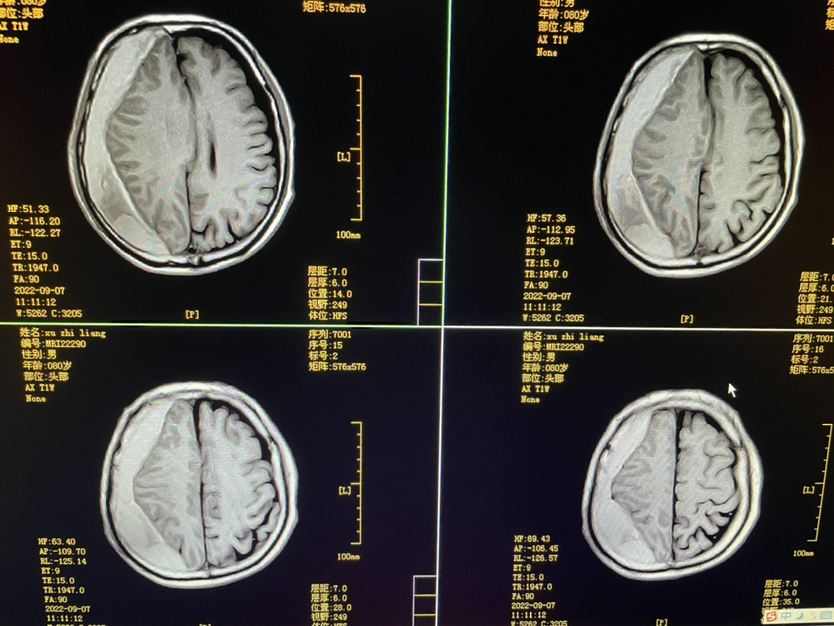

明确外伤史二月,80y,